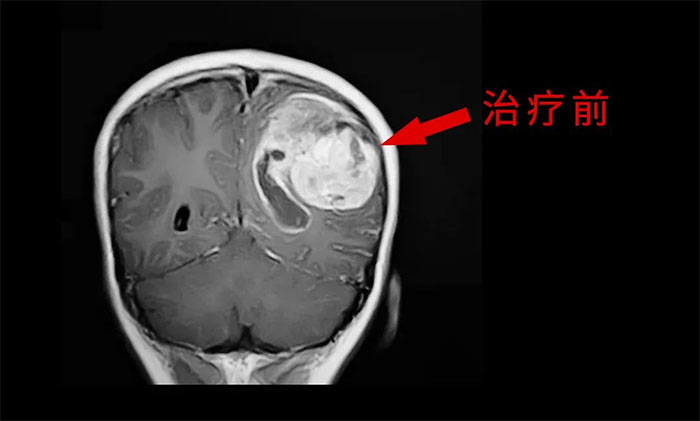

由于脑胶质瘤具有侵袭性、浸润性生长的特性,高级别胶质瘤与正常脑组织无明确边界,难以大范围彻底切除,残留的肿瘤细胞成为日后复发的根源,因此脑胶质瘤具有高复发率、高致残率的特征,严重影响患者的生活质量和生存周期,堪称“大脑杀手”。

外科手术往往是胶质瘤治疗的第一步。手术原则是在最大范围安全切除(maximal safe resection)肿瘤的同时,保护神经功能区。以解除占位征象和缓解颅内高压症状;解除或缓解因脑胶质瘤引发的相关症状;获得病理组织和分子病理,明确诊断;降低肿瘤负荷,为后续综合治疗提供条件。

于耀宇主任特别指出,随着脑血管介入技术快速发展,脑胶质瘤术后超选介入化疗联合同步放疗的效用正逐渐为大家所认识。超选介入化疗,是利用微导管技术直接将药物通过供血动脉,灌注到颅内肿瘤组织区域,避免了传统口服或静脉注射药物,要经过全身代谢后才能到达肿瘤区域。可减轻全身毒性反应,延长化疗药在肿瘤内的滞留时间,更好地杀伤肿瘤细胞。